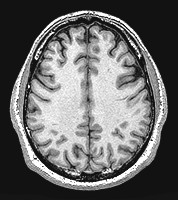

The two hemispheres of the brain, as seen in cross section from above, in a photo taken by an MRI machine.